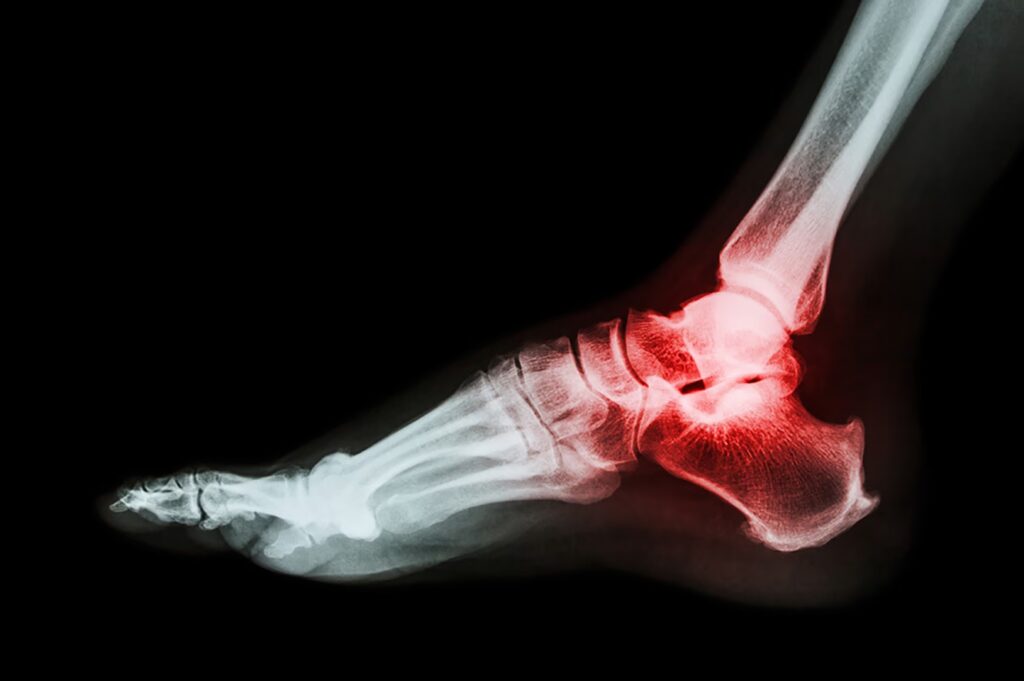

Ledsmerter kan opstå i alle kroppens led, herunder nakke, skuldre, hofter, knæ og hænder. Smerten beskrives ofte som øm, dunkende eller stikkende og kan forværres ved bevægelse. Mens akutte ledsmerter kan skyldes en skade og forsvinde af sig selv, er kroniske smerter ofte tegn på en underliggende inflammatorisk tilstand som gigt.

- Urinsyregigt (Podagra): En inflammatorisk gigtsygdom forårsaget af en ophobning af urinsyrekrystaller i leddene, oftest i storetåen. Dette fører til pludselige og intense smerteanfald.